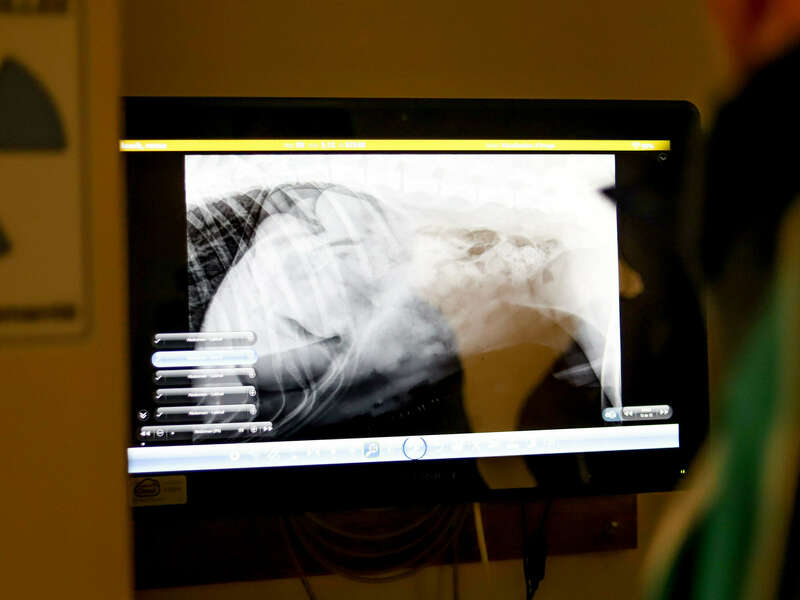

Radiographie numérique/ Échographie

La clinique vétérinaire dispose de son propre appareil de radiologie afin de réaliser rapidement les radiographies nécessaires au diagnostic des maladies et des fractures. Grâce à sa technologie capteur plan, on obtient immédiatement des images d'une qualité exceptionnelle. Les radiographies permettent le diagnostic des fractures mais aussi des maladies pulmonaires, cardiaques, digestives, urinaires et bien d'autres encore. Rapide et indolore, la radiographie est utilisée quotidiennement à la clinique.